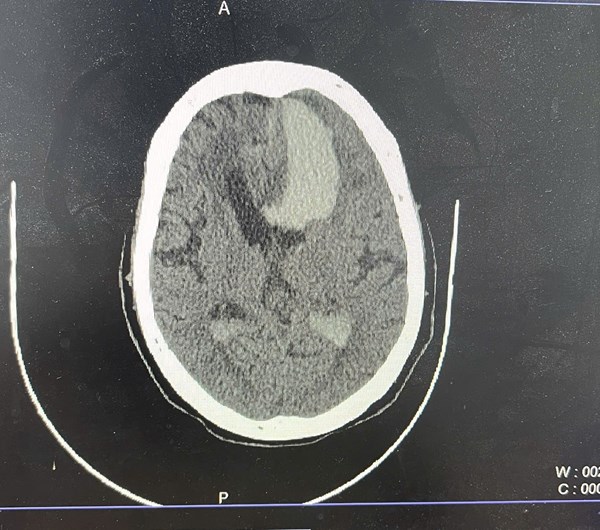

Figure 1. Non-contrast CT scan of the brain (axial view) demonstrates a large hyperdense hematoma in the left basal ganglia with extension into the left lateral ventricle. There is marked surrounding vasogenic edema, rightward midline shift, and compression of the contralateral lateral ventricle—findings consistent with mass effect and impending brain herniation.

The head CT performed shortly before arrest revealed a large hemorrhage in the left basal ganglia, extending into the lateral and third ventricles, accompanied by diffuse cerebral edema and significant midline shift. These findings were consistent with severe intracranial pathology and an acute elevation in intracranial pressure, leading to brain herniation and loss of circulatory function.